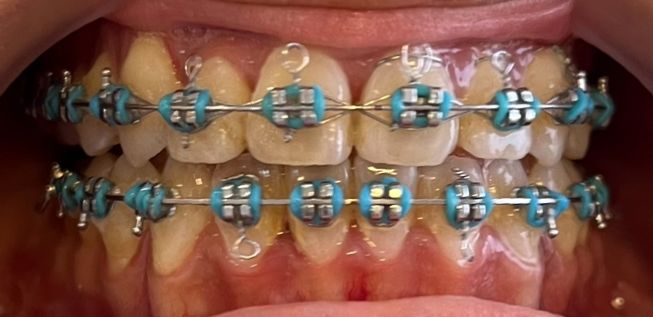

After

Before